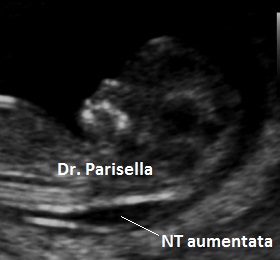

Quella che interessa dal punto di vista della diagnosi ecografica prenatale è l'Osteogenesi Imperfetta tipo II (OMIM 166210) caratterizzata da fragilità ossea con fratture multiple, micromelia severa dovuta alle fratture delle ossa lunghe, ipoplasia toracica severa a volte con fratture costali, ipomineralizzazione diffusa del cranio.  Ecograficamente si manifesta con ossa corte, ricurve e fratturate (le ossa fratturate si presentano angolate); ossa craniche scarsamente ossificate (tanto che la volta cranica può avere una ecogenicità simile a quella della linea mediana) con conseguente migliore evidenza e definizione delle strutture cerebrali e segno caratteristico la deformabilità della teca cranica.;  ipoplasia toracica con fratture costali; IUGR; movimenti fetali scarsi.